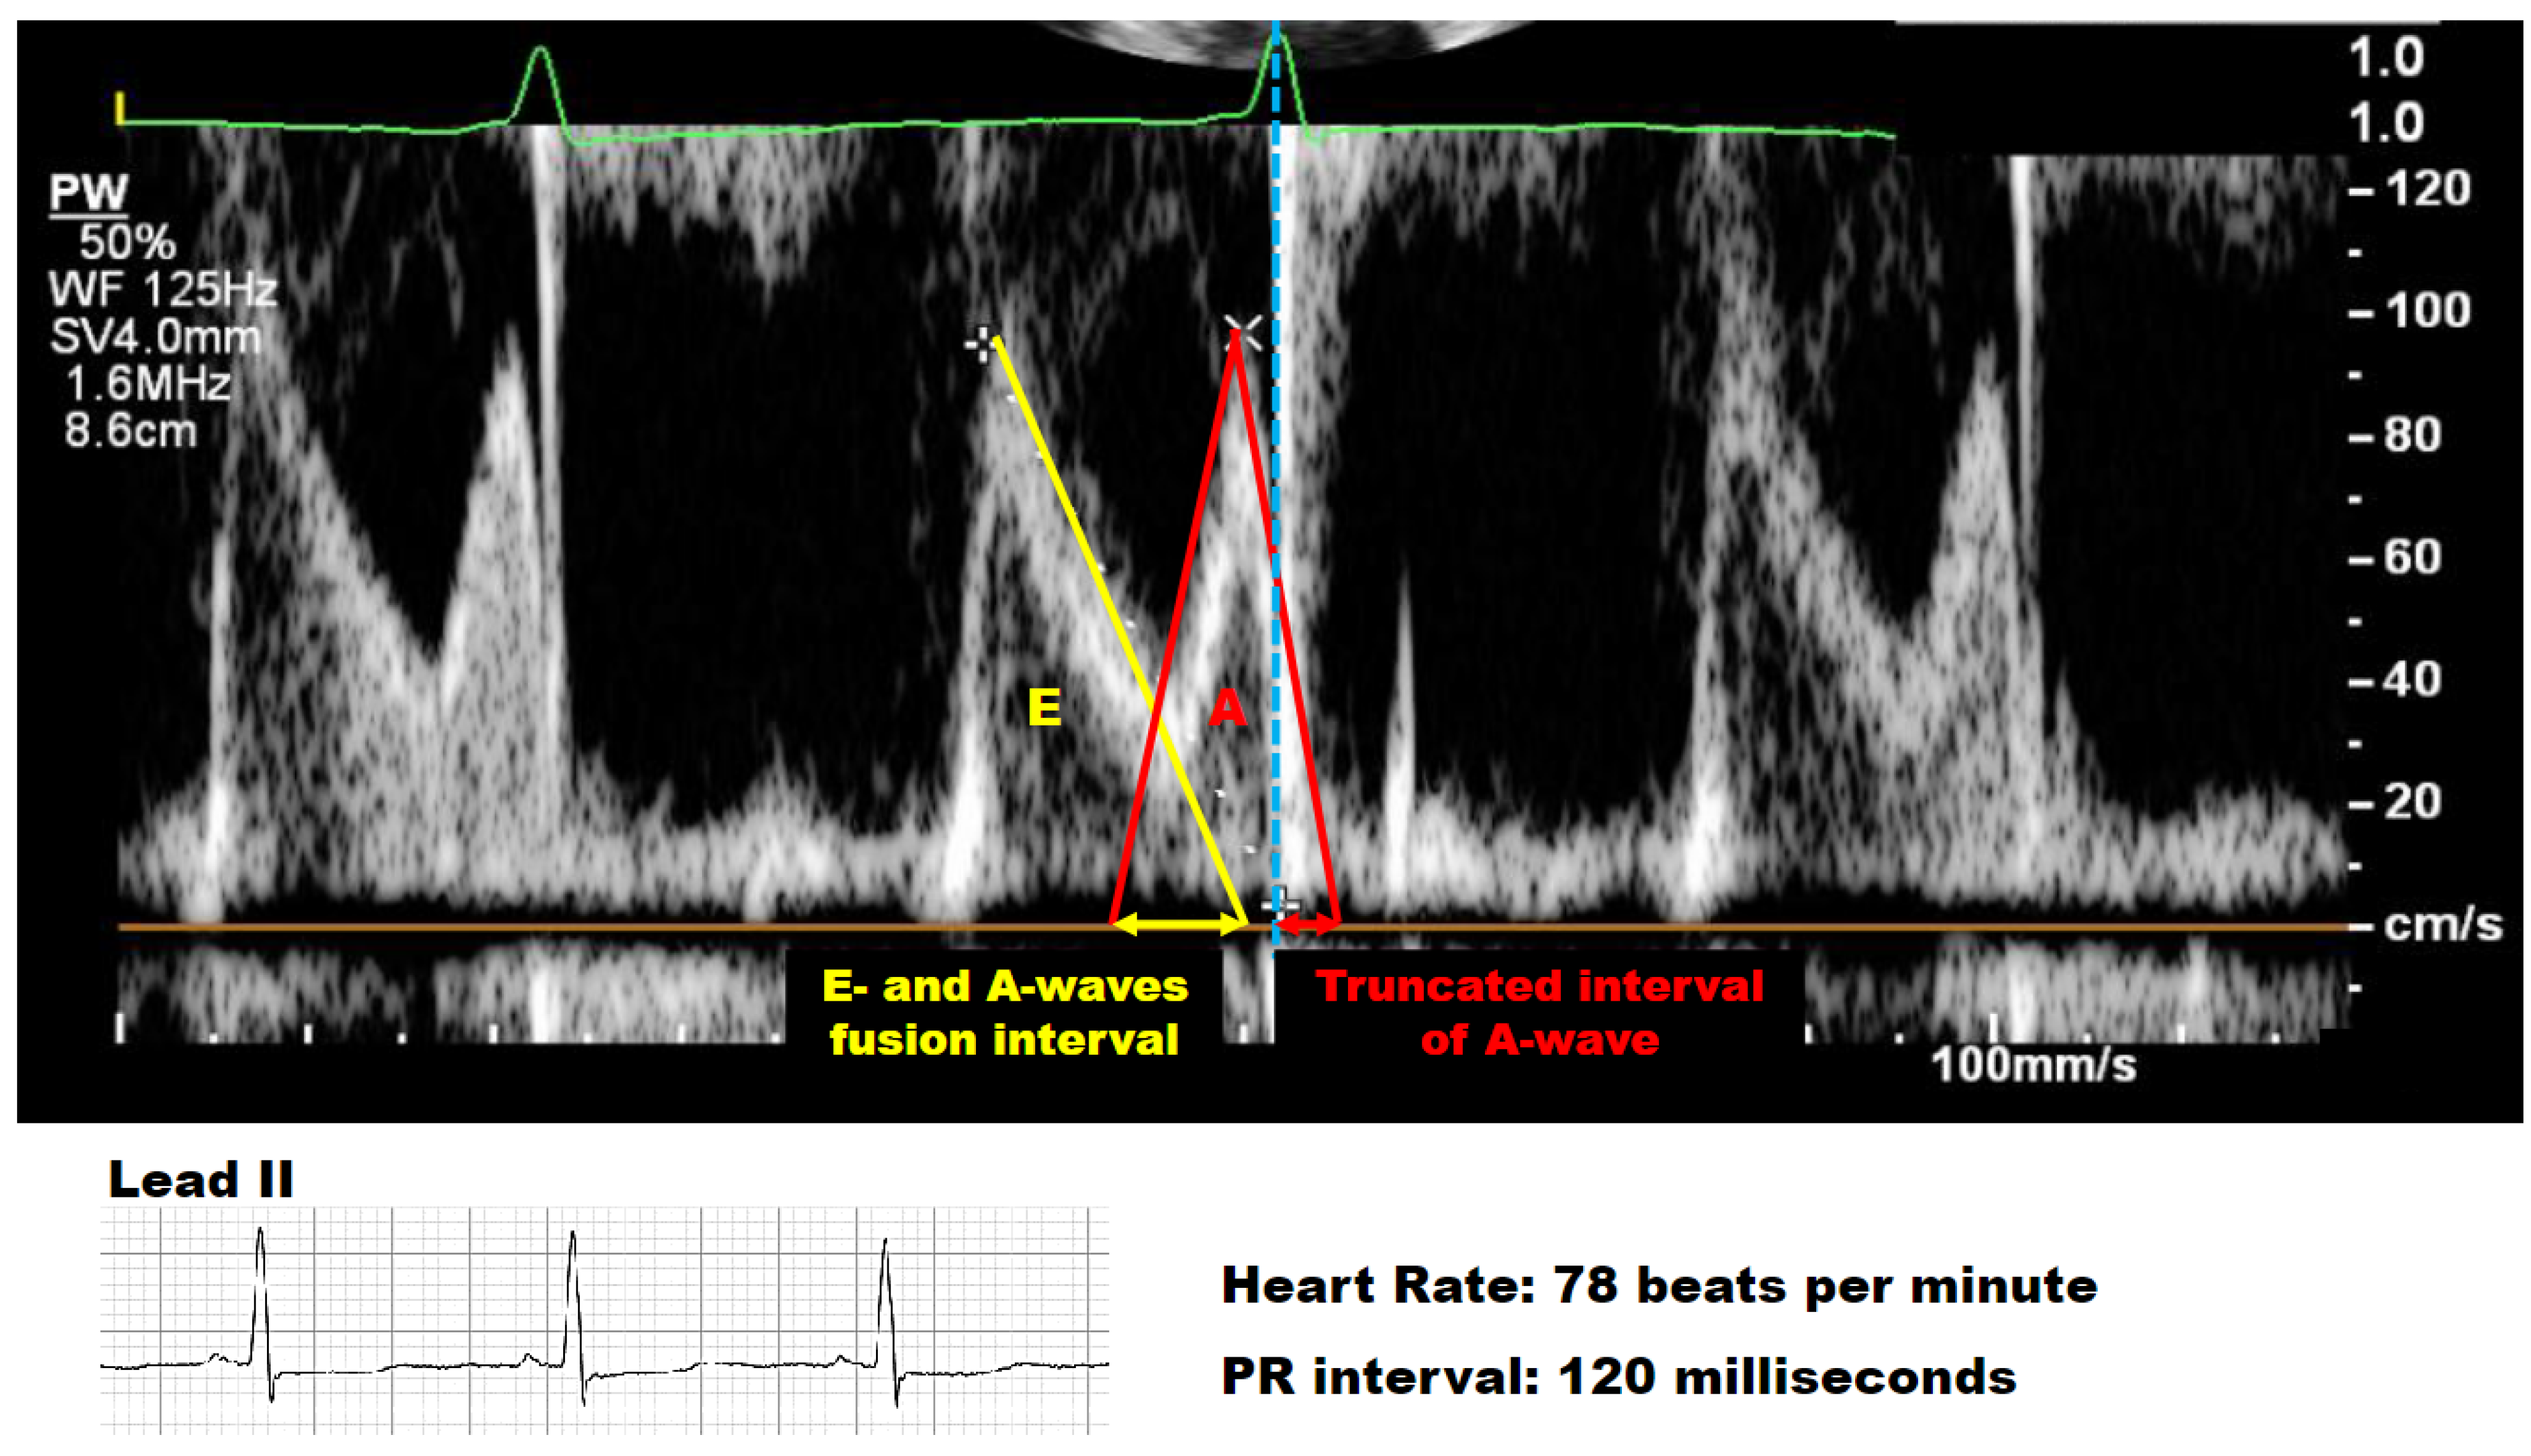

| Mitral E-wave speed, cm/sec | 30 [26–33] |

| Deceleration time to E-wave, msec | 185 [124–237] |

| Mitral A-wave speed, cm/sec | 64 [57–70] |

| Mitral E/A ratio | 0.9 [0.6–1.3] |

| Interval of E- and A-waves fusion, msec | 68 [33–103] |